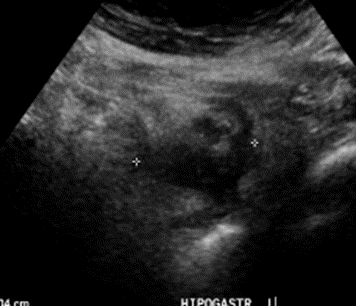

A nivel de hipogastrio se observa un engrosamiento focal de colon (colon sigmoide) con aumento de ecogenicidad de grasa adyacente, leve señal al doppler, doloroso al paso del transductor, podría corresponder a diverticulitis ¿? Tumoral ¿? Se sugiere complementar con TAC

A nivel de hipogastrio se observa un engrosamiento focal del colon sigmoides con aumento de la ecogenicidad de la grasa adyacente y leve señal y doloroso al paso del transductor

Impresión diagnóstica: Los hallazgos descritos a nivel de hipogastrio podrían estar en el contexto de un proceso inflamatorio intestinal inespecífico diverticulitis ¿? Tumoral ¿?